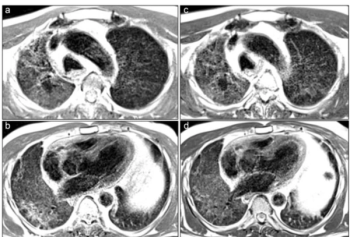

Emerging research with low-field MRI shows that persistently moderate to severe opacities were a common finding in patients up to two years after having acute COVID-19 pneumonia.